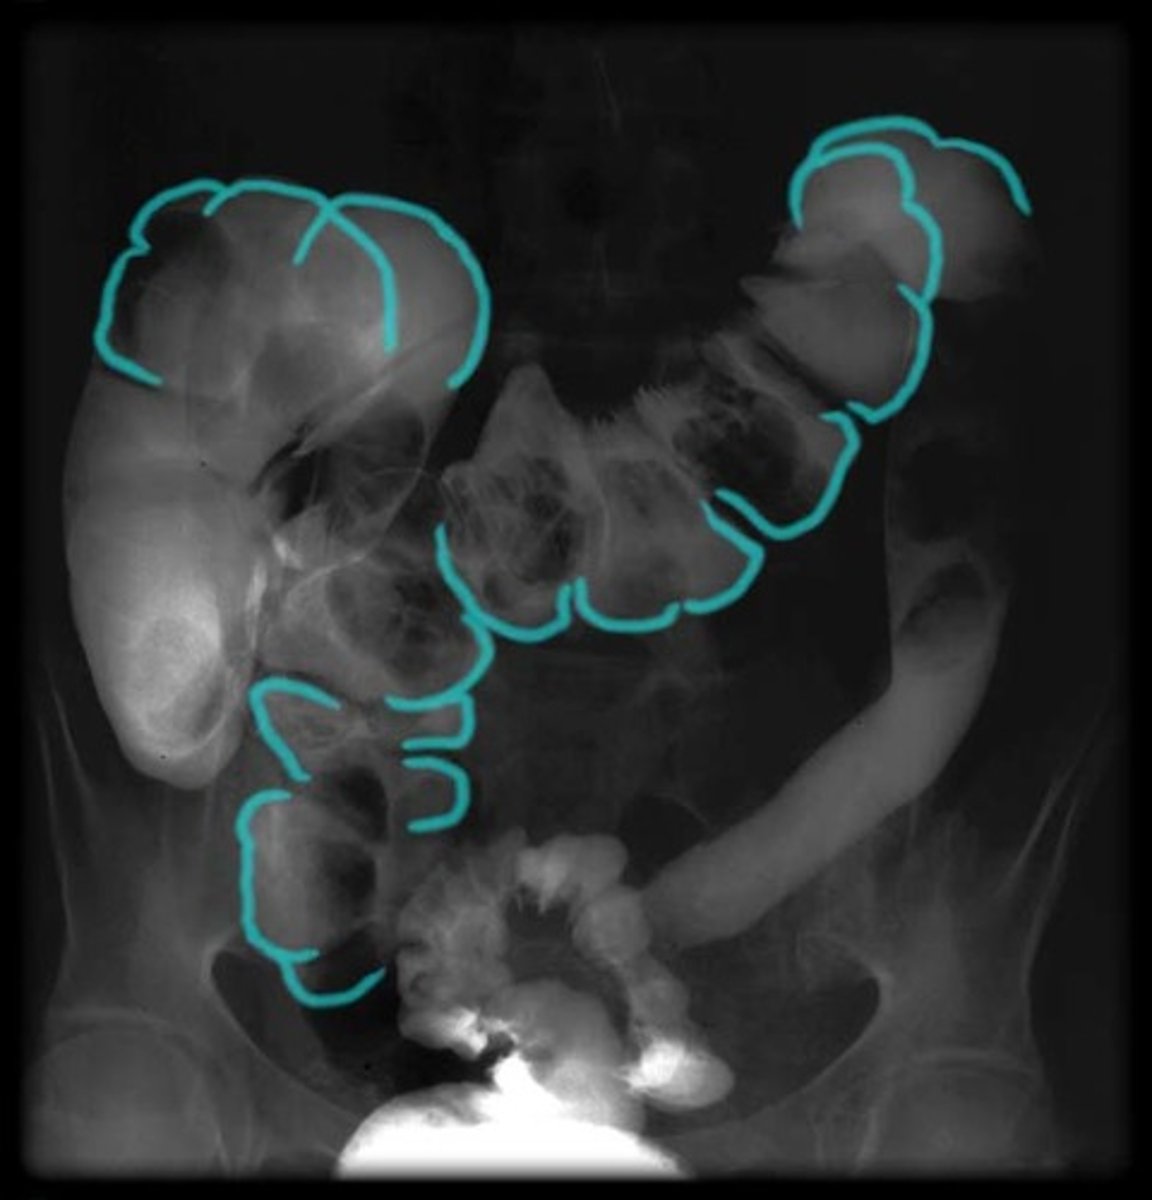

What is this?

Jejunum

Ileum

Ileocecal junction

Teniae coli

Haustra

Epiploic appendices

Cecum

Vermiform appendix

Ascending colon

Transverse colon

Descending colon

Sigmoid colon